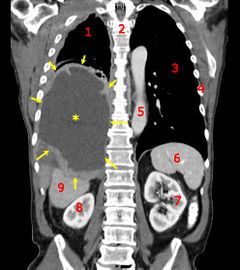

أشعة مقطعية إكليلية تظهر سرطان كيس الرئة الخبيث.

المفتاح: → ورم ←, ★ انصباب جنبي مركزي، 1&3 الرئتان، 2 العمود الفقري، 4 الضلوع، 5 الأورطى، 6 الطحال, 7&8 الكليتان، 9 الكبد.